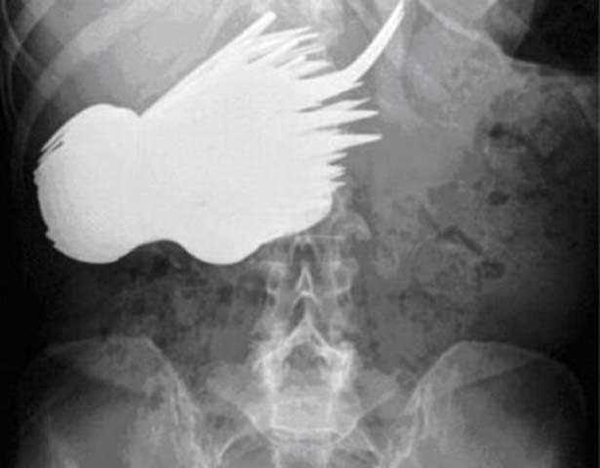

#4

Foto - 36 yıl sonra midesinden kardeşi çıktı!

Midesinden bir uçak çıktı - Fransız Michel Lotito, sürekli bir şeyleri yemesiyle ünlü. Takma adı Monsieur Mangetout yani Bay Her Şeyi Yiyen olan Lotito, bugüne kadar pek çok garip şeyi, parça parça yemesiyle tanınıyor. Bugüne dek Lotito'nun mideye indirdiği şeyler arasında 18 bisiklet, 15 alışveriş arabası, 7 televizyon, 6 avize, 2 yatak bulunuyor. Ancak bunlardan da ilginci, Lotito'nun 2 yıl uğraşarak bir Cessna tipi uçağı yemiş olması!